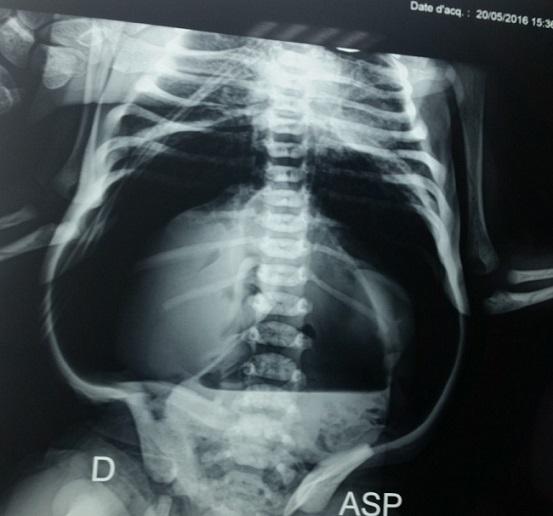

Spontaneous neonatal gastric perforation is rare. We report the case of a newborn without any abnormality identified at delivery and whose mother had problem-free pregnancy. On the third day of life, he had a sudden onset of severe abdominal distension followed by bilious vomiting. Abdominal X-rays without treatment showed massive pneumoperitoneum and laparotomy showed a perforation at the level of the anterior gastric wall closed in a single layer closure. Postoperative course was uneventful. Spontaneous neonatal gastric perforation usually has a favorable outcome. Hence the importance of early diagnosis and patient management.

新生儿自发性胃穿孔很罕见。我们报告一例新生儿病例,该新生儿出生时未发现任何异常,其母亲孕期也无问题。出生后第三天,他突然出现严重腹胀,随后出现胆汁性呕吐。未经治疗的腹部X线检查显示大量气腹,剖腹手术显示胃前壁水平有一个穿孔,采用单层缝合关闭。术后过程顺利。新生儿自发性胃穿孔通常预后良好。因此,早期诊断和患者管理非常重要。